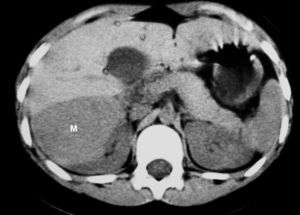

Fig. 9. Angiomiolipoma. Niña con esclerosis tuberosa. (A) Ecografía abdominal. Corte renal derecho. Masa renal de ecogenicidad heterogénea y contornos lobulados. (B) Tomografía computarizada abdominal. Masa (M) en riñón derecho. No se identifica componente graso. En el hígado existen tres lesiones de atenuación grasa correspondientes a angiomiolipomas hepáticos (1, 2, 3).